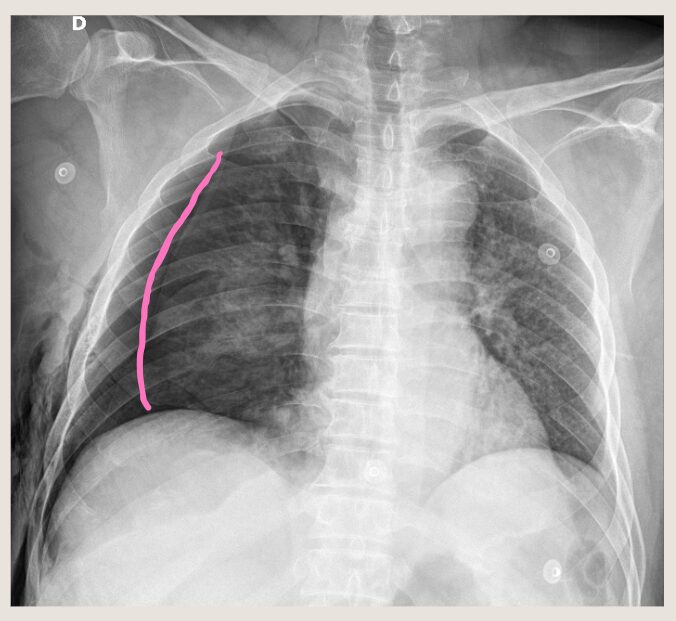

どうでしょうか? 右肺の上の方に、なんだか「線」が見えるでしょう?

さらに拡大しました。しぼんだ肺のラインが見えます!